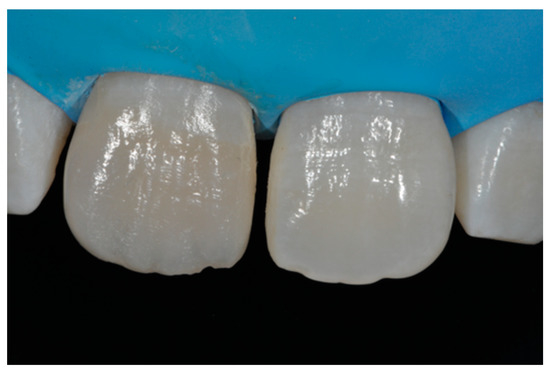

A healthy 38-year-old man referred to the dental office for the esthetic rehabilitation of left central maxillary incisor (Figure 41). Shade was selected as described in previous cases, using the button-try technique [14]. Isolation, preparation (Figure 42) and adhesive procedures were performed (Tokuyama Bond Force, Tokuyama Dental, Osaka, Japan). and Class III was restored on right central incisor (Asteria, A2B, Tokuyama Dental, Osaka, Japan). Frame was then completed on #2.1 (Figure 43) with the use of posterior sectional matrices using translucent and body material (Asteria, NE, A2B Tokuyama Dental, Osaka, Japan). After removing excesses both from the incisal margin and from the interproximal portion (Figure 44) silane and adhesive was applied strictly following the procedure described in Section 2.1.2. Dentinal body (Asteria, A2B, Tokuyama Dental, Osaka, Japan) was applied to reproduce internal anatomy (Figure 45) and then the external translucent enamel (Figure 46) (Asteria, NE, Tokuyama Dental, Osaka, Japan) was applied. The restoration shows good integration 6-months post-operative (Figure 47).

Figure 46.

External enamel layer is applied.

Figure 47.

Six months post-operative.